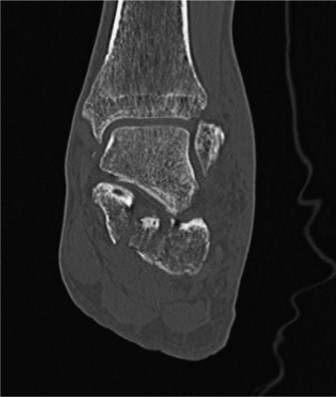

* Computed Tomography (CT) Scan: The gold standard for evaluating calcaneal fractures, especially intra-articular patterns. CT provides detailed information on articular involvement, comminution, fragment displacement, and subtalar joint congruity. 3D reconstructions are invaluable for pre-operative planning.

Figure 1: Axial CT scan demonstrating significant intra-articular calcaneal fracture with widening and displacement of the posterior facet.